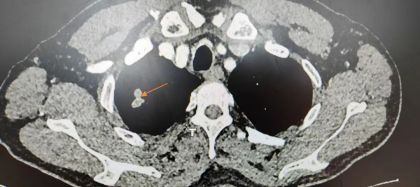

在体检过程中,一个危险的“信号”悄然浮现——CT影像显示李先生“右肺上叶见深分叶片状密度增高影,约1.5cm*1.5cm*2.1cm大小,双肺多发磨玻璃结节影。”,立即行增强CT检查,进一步明确了检查结果。

图|李先生体检时的CT影像